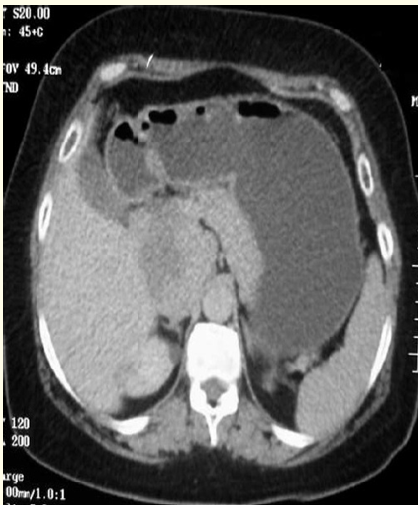

A Rare Giant Pericardial Cyst with Atypical Clinical Presentation- A Case Report

Dabeluchi Chiedozie Ngwu and Nicholas A Kerna